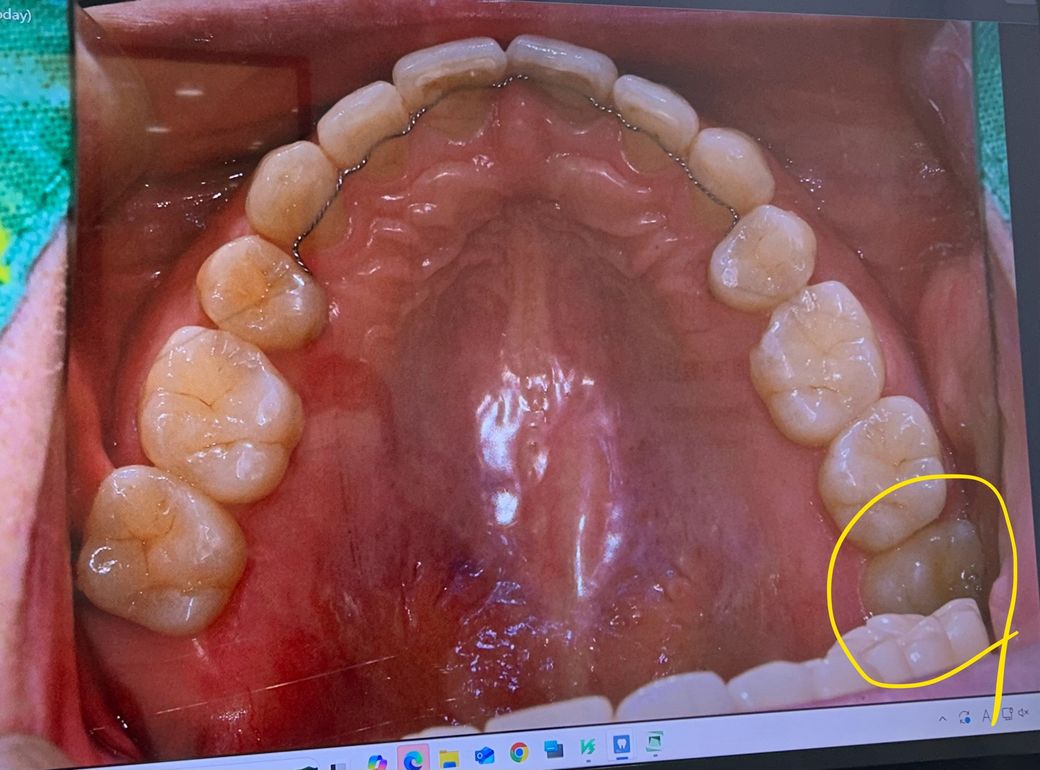

사랑니 빼야 할까요? 판단좀 부탁드립니다.

1. (노란 동그라미) 사랑니는 다 나온건지도 모르겠는데, 빼야할까요? 옆으로 삐뚤게 나긴 했는데, 충치는 없어요. 옆 어금니를 더 밀어버리거나 하는 등의 부작용이 있을까요?

• 1번 째 사진